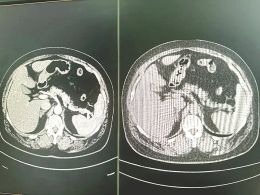

家住浙江宁波的57岁邱先生对《每日经济新闻》记者回忆称:2025年8月,其因患糖尿病,在宁波大学附属人民医院做了一次常规检查,并拍摄了腹部平扫CT。午饭时,他接到医院打来的电话:“你的胰腺可能有点问题,需要进一步检查。”电话那头是该院的副院长、肝胆胰外科主任医师朱柯磊。

据邱先生介绍,医生在电话里并未明说是什么问题,但其心里清楚“肯定不是好消息”。其迅速做了增强核磁共振检查(MRI),并于第二天接受了微创手术。朱柯磊医生还告诉邱先生,“你和乔布斯得了一样的病,但你比乔布斯幸运得多”。

据《每日经济新闻》记者了解,救了邱先生一命的,是阿里巴巴达摩院研发的胰腺癌AI早筛模型——PANDA。该AI模型从邱先生那张看似并无异常的平扫CT影像中,捕捉到了癌变的迹象。

朱柯磊医生向《每日经济新闻》记者介绍称,自2024年11月PANDA模型在宁波大学附属人民医院部署以来,已经分析了超过18万张CT影像,帮助医生发现了24例胰腺癌病例,其中14例为早期。在这14例早期患者中,有11人的平扫CT报告无异常提示,经AI预警召回后,进一步检查才得以确诊。

然而,由于胰腺与周围组织对比度低,在平扫CT影像上难以看清。微小的早期肿瘤更是如同“隐形”一般,极难被人眼发现。因此,“平扫CT无法用于早期胰腺癌筛查”曾是放射科的普遍共识。

据《每日经济新闻》记者了解,经过近两年训练,PANDA模型学会了识别平扫CT影像上那些微妙的密度变化、纹理异常和结构扭曲——这些特征虽难以被肉眼察觉,却是早期胰腺癌的蛛丝马迹。